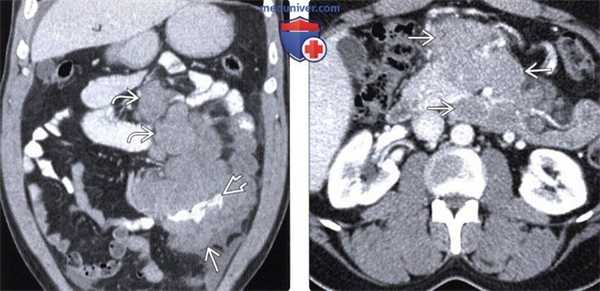

(Слева) На изображении в коро-нальной плоскости при КТ с контрастным усилением определяется диффузное опухолевидное утолщение стенки и расширение тонкого кишечника в левом нижнем квадранте, видно также контрастное вещество в просвете кишки. Чуть выше обратите внимание на выраженную лим фаденопатию. Эти изменения обусловлены подтвержденной биопсией СПИД-детерминированной неходжкинской лимфомой.

(Справа) На аксиальном срезе при КТ с контрастом определяется выраженная мезентериальная лимфаденопатия, обусловленная СПИД-детерминированной неходжкинской лимфомой.